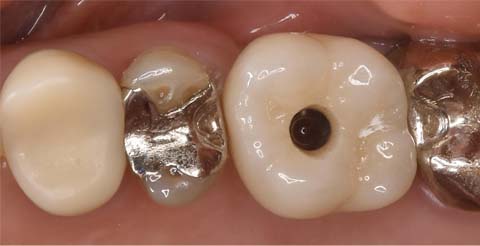

治療終了後の口腔内写真。

インプラント治療と並行して、銀歯を無くすメタルフリー治療も行いました。